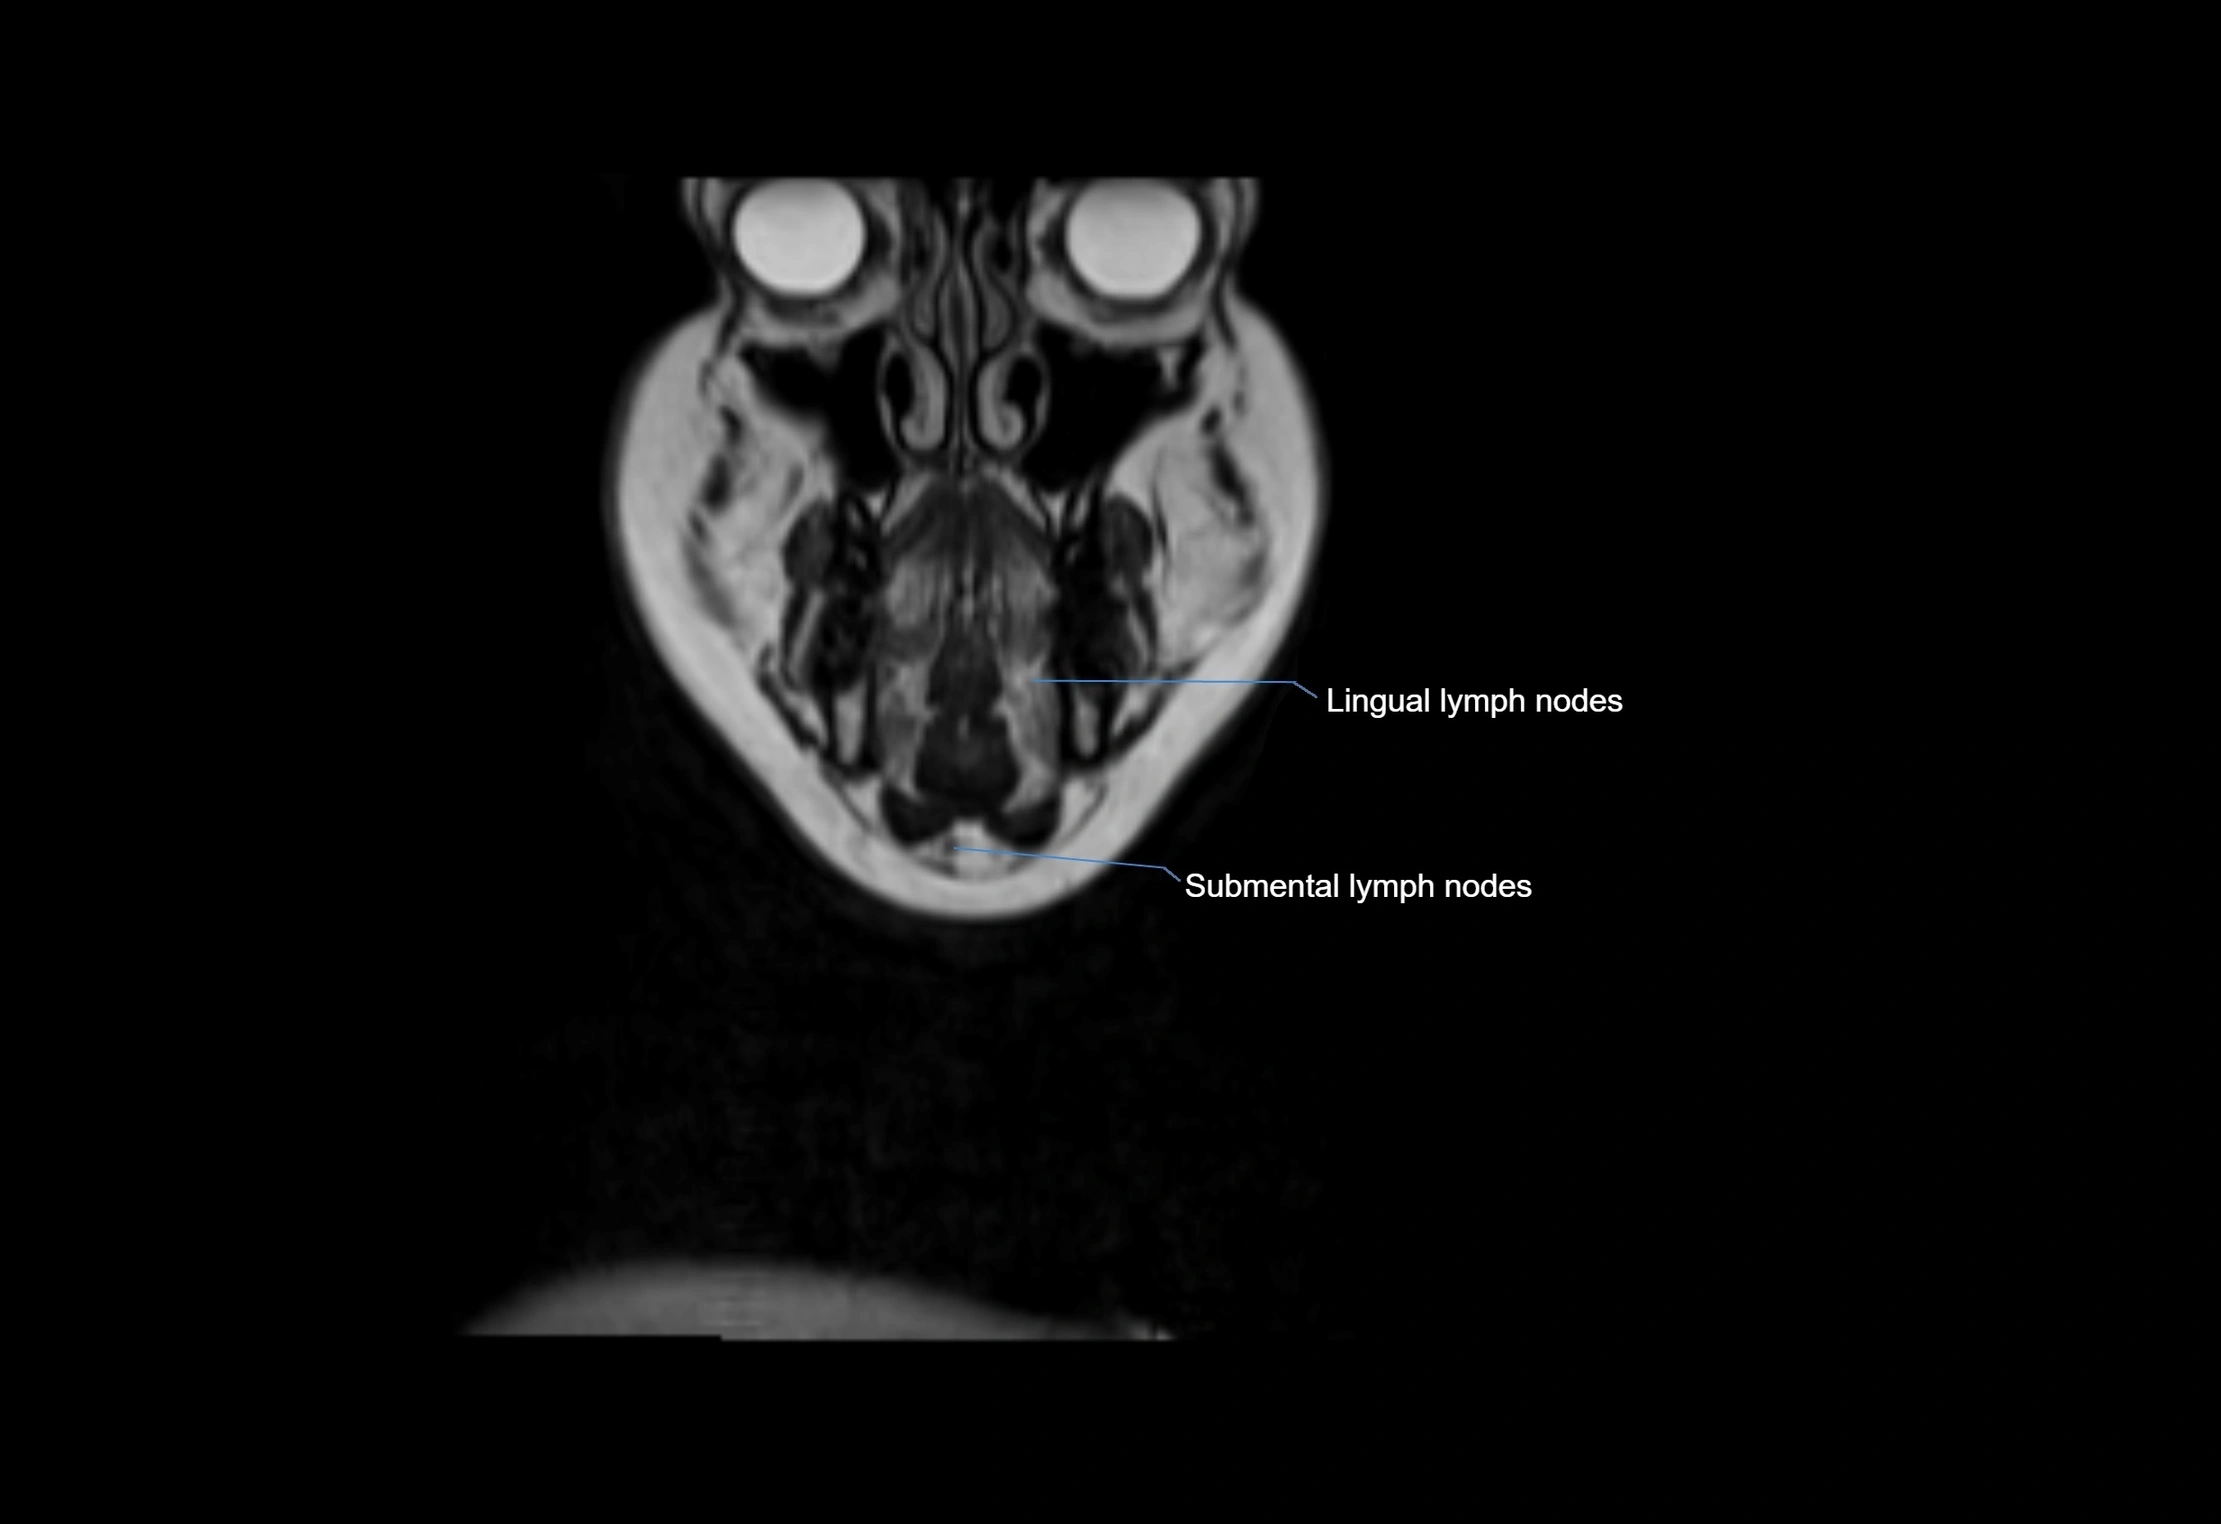

Location

• Found along primary lymph node chains, including preauricular, submandibular, parotid, and occipital regions

• Embedded in subcutaneous fat or superficial fascia, often lateral or posterior to primary nodes

MRI Appearance

T2-weighted images:

• Nodes show intermediate signal, with surrounding fat bright

• Useful for detecting edema, inflammation, or infiltration

• Fatty hilum may appear slightly hyperintense relative to cortex

MRI images